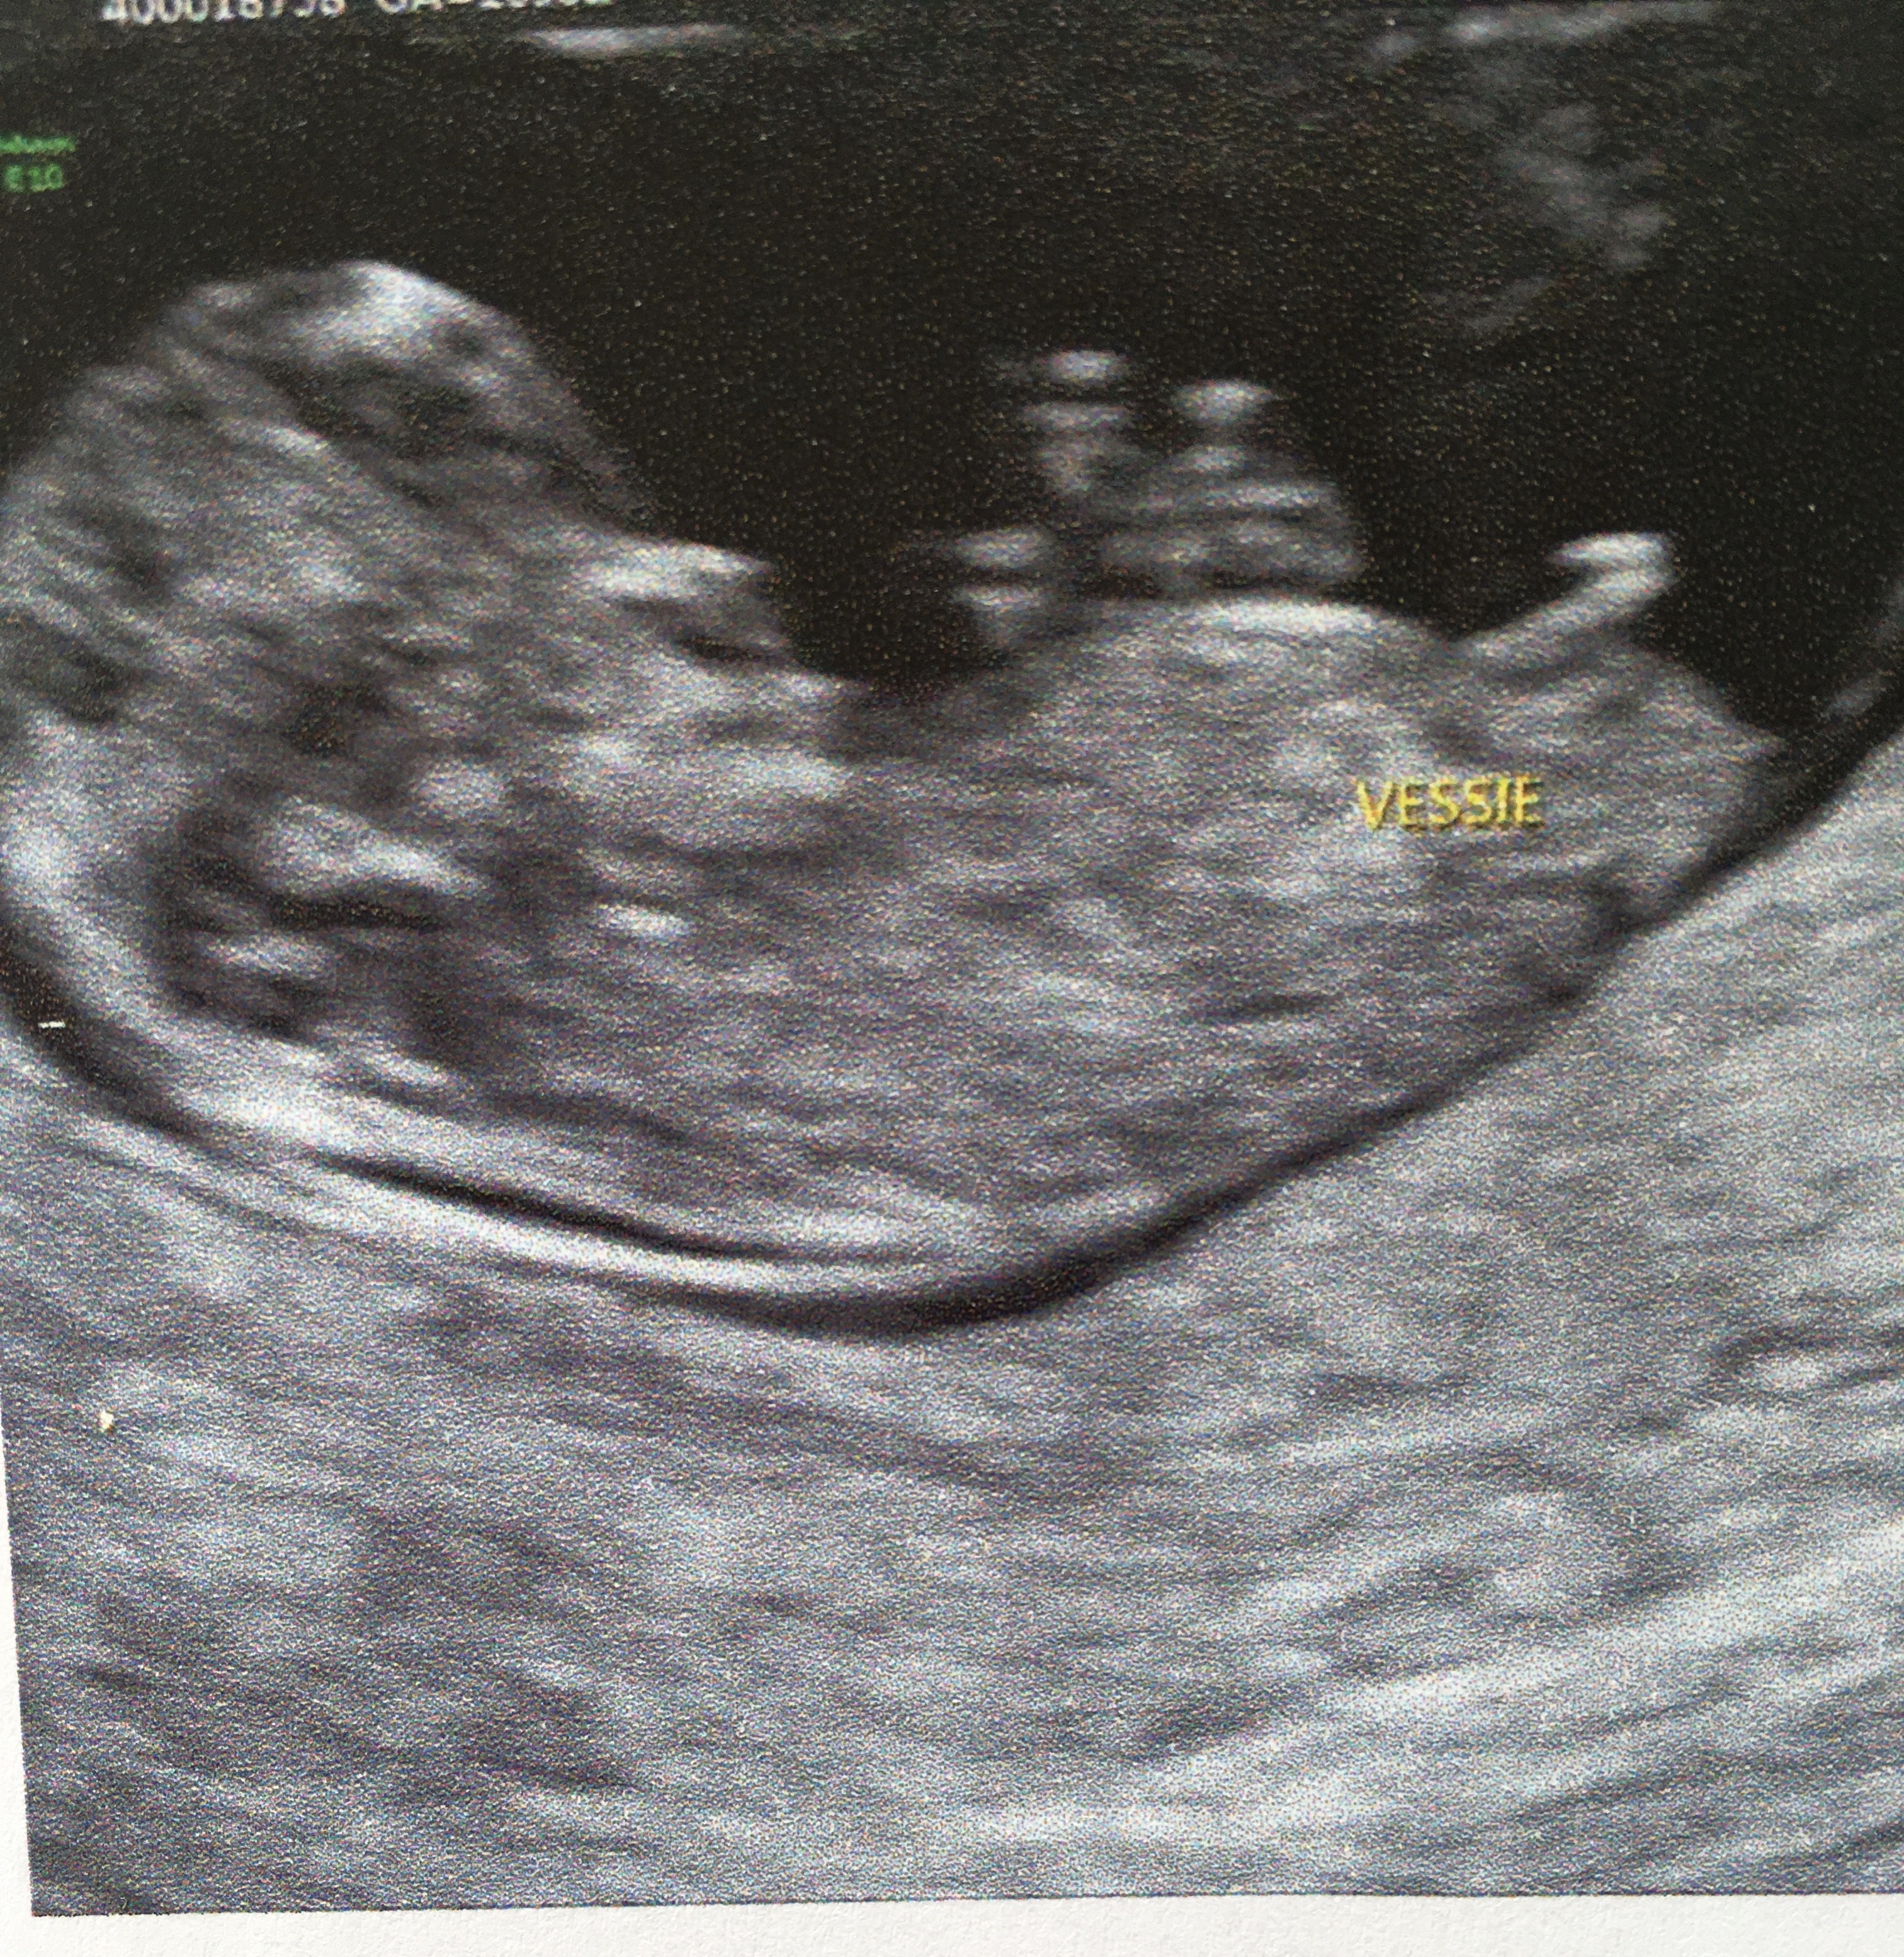

De votre bébé, qui se transformera au cours du deuxième trimestre en pénis chez les garçons ou en clitoris chez les filles Mais au début de la grossesse, le bourgeon ne présente aucune différenceDéposez vos fichiers ou Cliquez Date de début de grossesseEchographie du petit garcon de Francois et Genevieve ;)

Tubercule génital) Ce bourgeon est l'organe sexuel indéterminéDu tubercule d'une petite fille Néanmoins, ilTubercule génitale 1 article Toi aussi tu voudrais pouvoir connaître le sexe de bébé

Jour le Définition du terme Tubercule génital Précurseur au niveau de la zone génitale externe du futur clitoris ou du pénis3 ans Alimentation bébéTout d'abord, la grosseur du tubercule n'a rien à